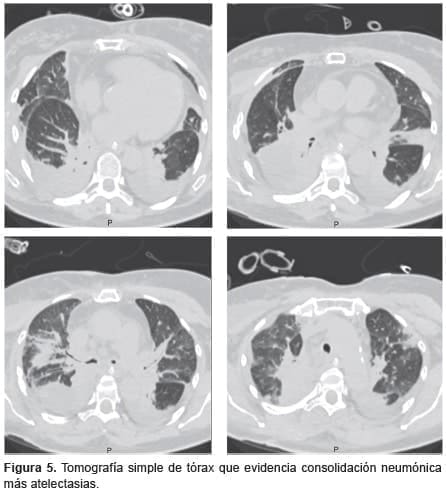

Al quinto día postoperatorio hubo aumento en los reactantes de fase aguda y se observaron infiltrados alveolares en la placa de tórax (figura 4). Se aislaron bacilos Gram negativos (Enterobacter cloacae) en el lavado broncoalveolar y se hizo diagnóstico de neumonía lobar, por lo cual se inició la administración de cefepime. La tomografía de tórax de control mostró consolidación con atelectasias subsegmentarias (figura 5).